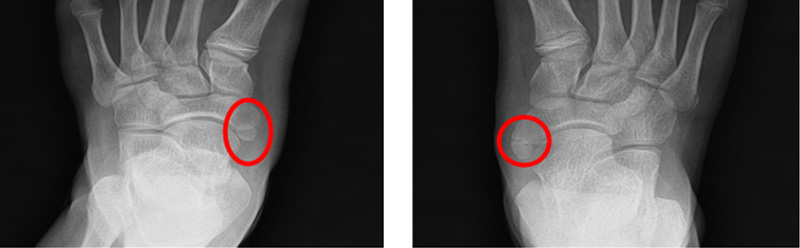

아킬레스 짦음증이 있는 아이들은 자주 발목이나 종아리가 아프다고 하며, 아픈 부위를 특정하지 못하고 다리가 아프다고 하며 내원합니다. 가끔은 발 뒤꿈치를 들고 걷는다고 하거나 까치발로 걷는다고 내원하기도 합니다. 걷는 자세는 주로 팔자걸음에 상체를 흔들면서 걷습니다. 이런 아이들은 좀 더 크면 무릎이나 허리를 아파하기도 합니다. 어린아이들의 경우에는 X-ray 등에도 이상 소견이 보이지 않아 주로 성장통이라고 오진을 받기도 합니다. 저희 병원에서는 현재 이에 대한 연구를 진행하고 있으며, 이런 아이들의 대략 60% 정도에서 비만이 있고, 이러한 비만아이들은 골연령이 약 1.5세 정도 증가하게 되어 성인예측키에서 약 3~4cm 정도의 손실이 발생합니다. (이상은 본원에서의 미발표 연구결과입니다)

아킬레스 짧음증 : 자주 발목이나 종아리 통증을 호소, 아픈부위를 특정하지 못하며 다리가 아프다고 호소. 9세 이후에도 까치말로 걷는등의 증상호소.